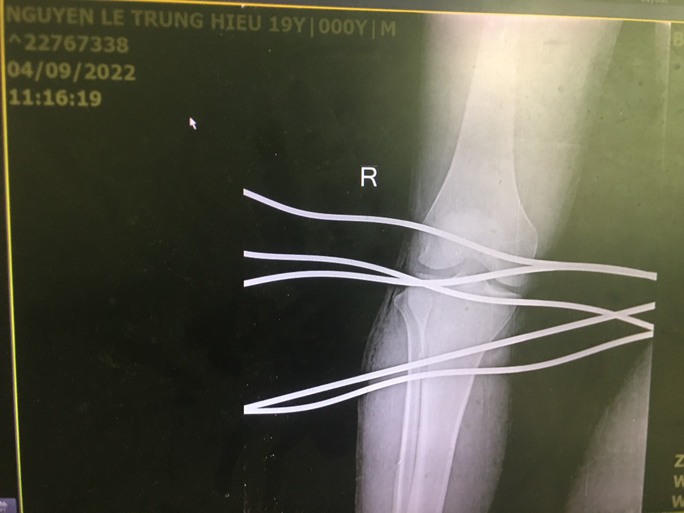

06/09/2022 05:00Kinh hoàng cảnh thanh niên bị 5 cây sắt đâm xuyên qua chân

Ngày 5-9, Bệnh viện Đa khoa Trung ương Quảng Nam (đóng tại huyện Núi Thành) cho biết sau khi phẫu thuật lấy 5 thanh sắt ra khỏi chân, sức khỏe anh N.L.T.H (19 tuổi; trú huyện Sơn Tịnh, tỉnh Quảng Ngãi) đang dần ổn định.

Trước đó, ngày 4-9, anh H. được đưa vào cấp cứu trong tình trạng bị 5 thanh sắt đâm thủng xuyên qua chân. Theo anh H., trong quá trình kéo cáp bằng máy tại công ty, dây cáp bất ngờ bị đứt khiến các thanh sắt rơi xuống. Có tổng cộng 5 thanh sắt đâm vào chân nam thanh niên này.

Sau khi tiếp nhận bệnh nhân, các bác sĩ đã nhanh chóng sơ cứu và hội chẩn chuyên khoa Ngoại chấn thương xử trí cấp cứu. Sau hơn 1 giờ, 5 thanh sắt đã được ê kíp lấy ra khỏi chân của nam thanh niên.

Bác sĩ Trình Anh Hoàng, người trực tiếp phẫu thuật cho H., cho biết đây là tai nạn hy hữu, may mắn là anh được đưa đến bệnh viện phẫu thuật cấp cứu kịp thời.

Theo bác sĩ Hoàng, đối với các trường hợp bị vật nhọn đâm vào cơ thể, cần nhanh chóng đưa nạn nhân đến cơ sở y tế gần nhất để xử lý, tuyệt đối không được rút dị vật ra vì có thể làm tổn thương mạch máu, thần kinh trầm trọng thêm hoặc nguy hiểm hơn, bệnh nhân có thể chết vì chảy máu ồ ạt.